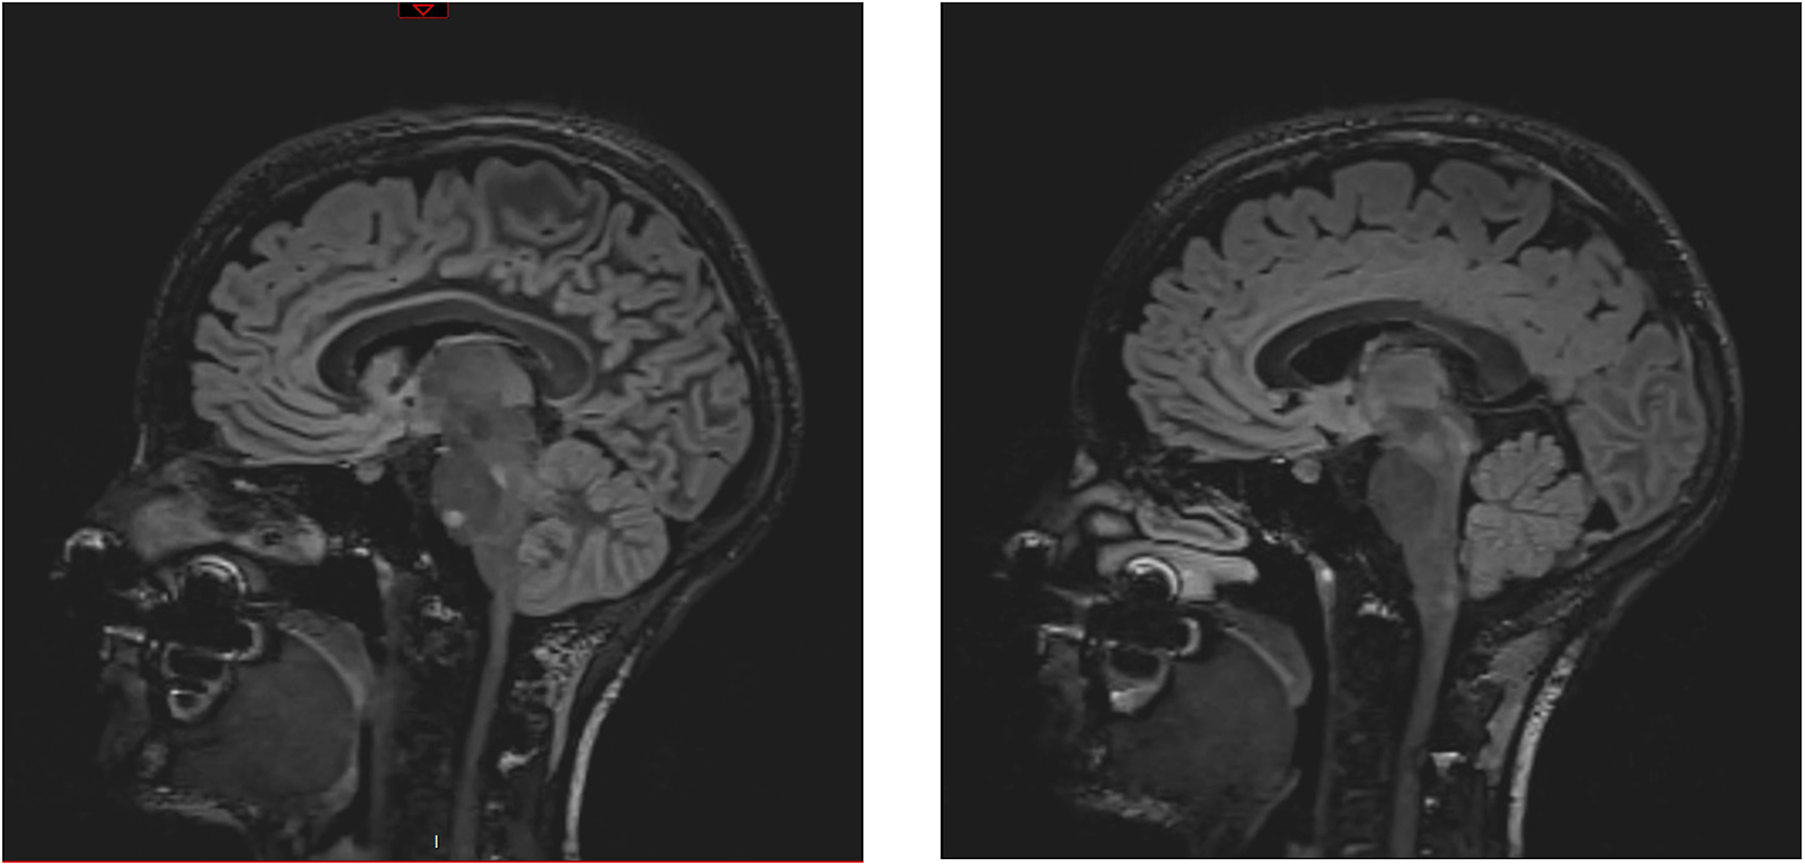

An athletic 26-year-old woman was admitted to the emergency department of a Swiss secondary-level care hospital for new-onset numbness in the lower limbs. Initial neurological examination showed lower limb hypoesthesia up to the tenth dorsal level. Spinal magnetic resonance imaging (MRI) showed a T2 lesion at D12 level without contrast enhancement. Cerebral MRI revealed multiple demyelinating lesions, three of which were located in the brainstem (Figure 1: Cerebral magnetic resonance imaging (T2-flair) performed at day one showing three demyelinating in the brainstem). A lumbar puncture was performed and showed IgG oligoclonal bands with no other abnormality. Urinary pregnancy test was negative. At the time of her admission, apart from the neurological symptoms, she was asymptomatic and in a stable hemodynamic condition. During the course of the night, she was woken up by sudden unbearable holo-cranial pulsatile headache associated with hypertension, with systolic values up to 220 mmHg. She quickly developed chest pain, dyspnea and oxygen saturation dropped to 70% in ambient air. Initial arterial blood gases showed severe hypoxemia, with an oxygen partial pressure of 42 mmHg and lactic acidosis with a pH of 7.30 (N: 7.37–7.45) and an arterial lactate level of 5.3 mmol/L (N < 2.0 mmol/L). An ECG showed ST-segment depression in the inferior (II-III-aVF) and precordial (V3 through V6) leads (Figure 2: Electrocardiogram performed at day 1 revealing ST-segment depression in the inferior (II-III-aVF) and precordial (V3 through V6) leads). QTc time was measured at 400 ms. Serum high sensitivity (hs) T-troponins were elevated to 438 ng/L (N < 14 ng/L) and D-Dimers were measured at 20818 µg/L (N < 500 µg/L), without NT-proBNP elevation (value: 58 ng/L). Hematological testing was relevant for important leukocytosis of 23.2 G/l (N: 4–10 G/L) with 76% of segmented neutrophils as well as hemoconcentration with a hemoglobin level of 176 g/L (N: 120–157 g/L) and a hematocrit value of 0.52 L/L (N: 0.35–0.47 L/L). However, there was no evidence of active infection with a CRP level below the threshold of 5 mg/L and the absence of fever. The clinical condition worsened thereafter, with acute respiratory failure and hemodynamic instability, with sinus tachycardia (heart rate up to 150/min), requiring a transfer to the intensive care unit for urgent orotracheal intubation. During orotracheal intubation, blood pressure plummeted to a nadir of 59/44 mmHg, requiring aminergic support. Chest radiograph revealed acute pulmonary edema.

Figure 1

Cerebral magnetic resonance imaging (T2-flair) performed at day one showing three demyelinating in the brainstem.